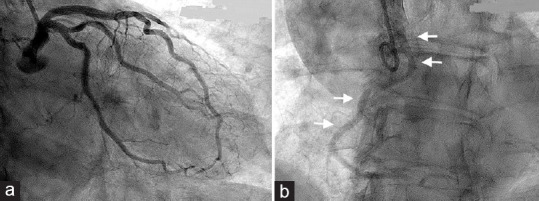

This case report presents a rare scenario involving a congenital anomaly of the right coronary artery's (RCA) origin in association with an ascending aortic aneurysm. While both anomalies are individually recognized in the literature, their coexistence and potential interplay remain understudied. The aim of this report is to emphasize the challenges and implications associated with such a combination. A 78-year-old male patient with an enlarged ascending aortic aneurysm necessitating surgical intervention was found to have an anomalous origin of the RCA during preoperative coronary angiography, confirmed by computed tomography scan. Transesophageal echocardiography further elucidated the coronary abnormality. Intraoperatively, successful aortic replacement was performed, and careful repositioning of the anomalous right coronary ostium was achieved. This case raises important considerations regarding the potential complications arising from coronary anomalies and their impact on the surgical management of ascending aortic aneurysms. The rarity of this combination limits our understanding of their association, making a multidisciplinary approach crucial for optimal patient care. Further research and comprehensive evaluation of similar cases are necessary to better understand the relationship between coronary anomalies and ascending aortic aneurysms. Such investigations will help in improving treatment strategies and outcomes for patients with these complex conditions.